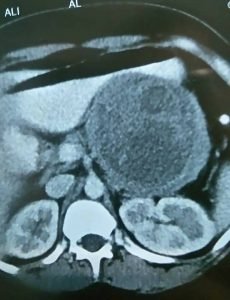

و أيضاً هناك إهتمام منا بنوعية من أورام البنكرياس وهي أورام البنكرياس الكيسية Pancreatic Cystic Neoplasmas وهذه الأورام تكون علي هيئة أكياس في البنكرياس وهناك اهتمام عالمي بها في الآونة الأخيرة نظراً لزيادة معدل إكتشاف هذه الأورام الكيسية وذلك بإستخدام وسائل التشخيص بالأشعة الحديثة مثل الأشعة المقطعية والأشعة بالرنين المغناطيسي والأشعة بالموجات فوق الصوتية بالمنظار مع إمكانية أخذ عينات بواسطة إبرة دقيقة من هذه الأورام لتحليل السائل والخلايا والأنسجة الموجودة في هذه الأورام.

وهناك أنواع مختلفة من هذه الأورام الكيسية فعلي سبيل المثال هناك الاورام الكيسية المصلية Serous Cystic Neoplasmas وهناك الأورام الكيسية المخاطية مثل Mucinous Cystic Neoplasmas وكذلك Intraductal Papillary Mucinous Neoplasmas وهناك الأورام الصماء الكيسية Solid Cystic Pseudopapillary Neoplasmas وهناك أورام أخري لايتسع المجال هنا لذكرها.

وعلاج هذه الأورام يحتاج إلى التشخيص الدقيق وإجراء العملية الجراحية المناسبة حسب نوع وحجم ومكان الورم وحسب نوعية الخلايا الموجودة في الورم سواء كانت حميدة أم خبيثة ودرجتها، وكذلك حسب عمر المريض أو المريضة والحالة الصحية.